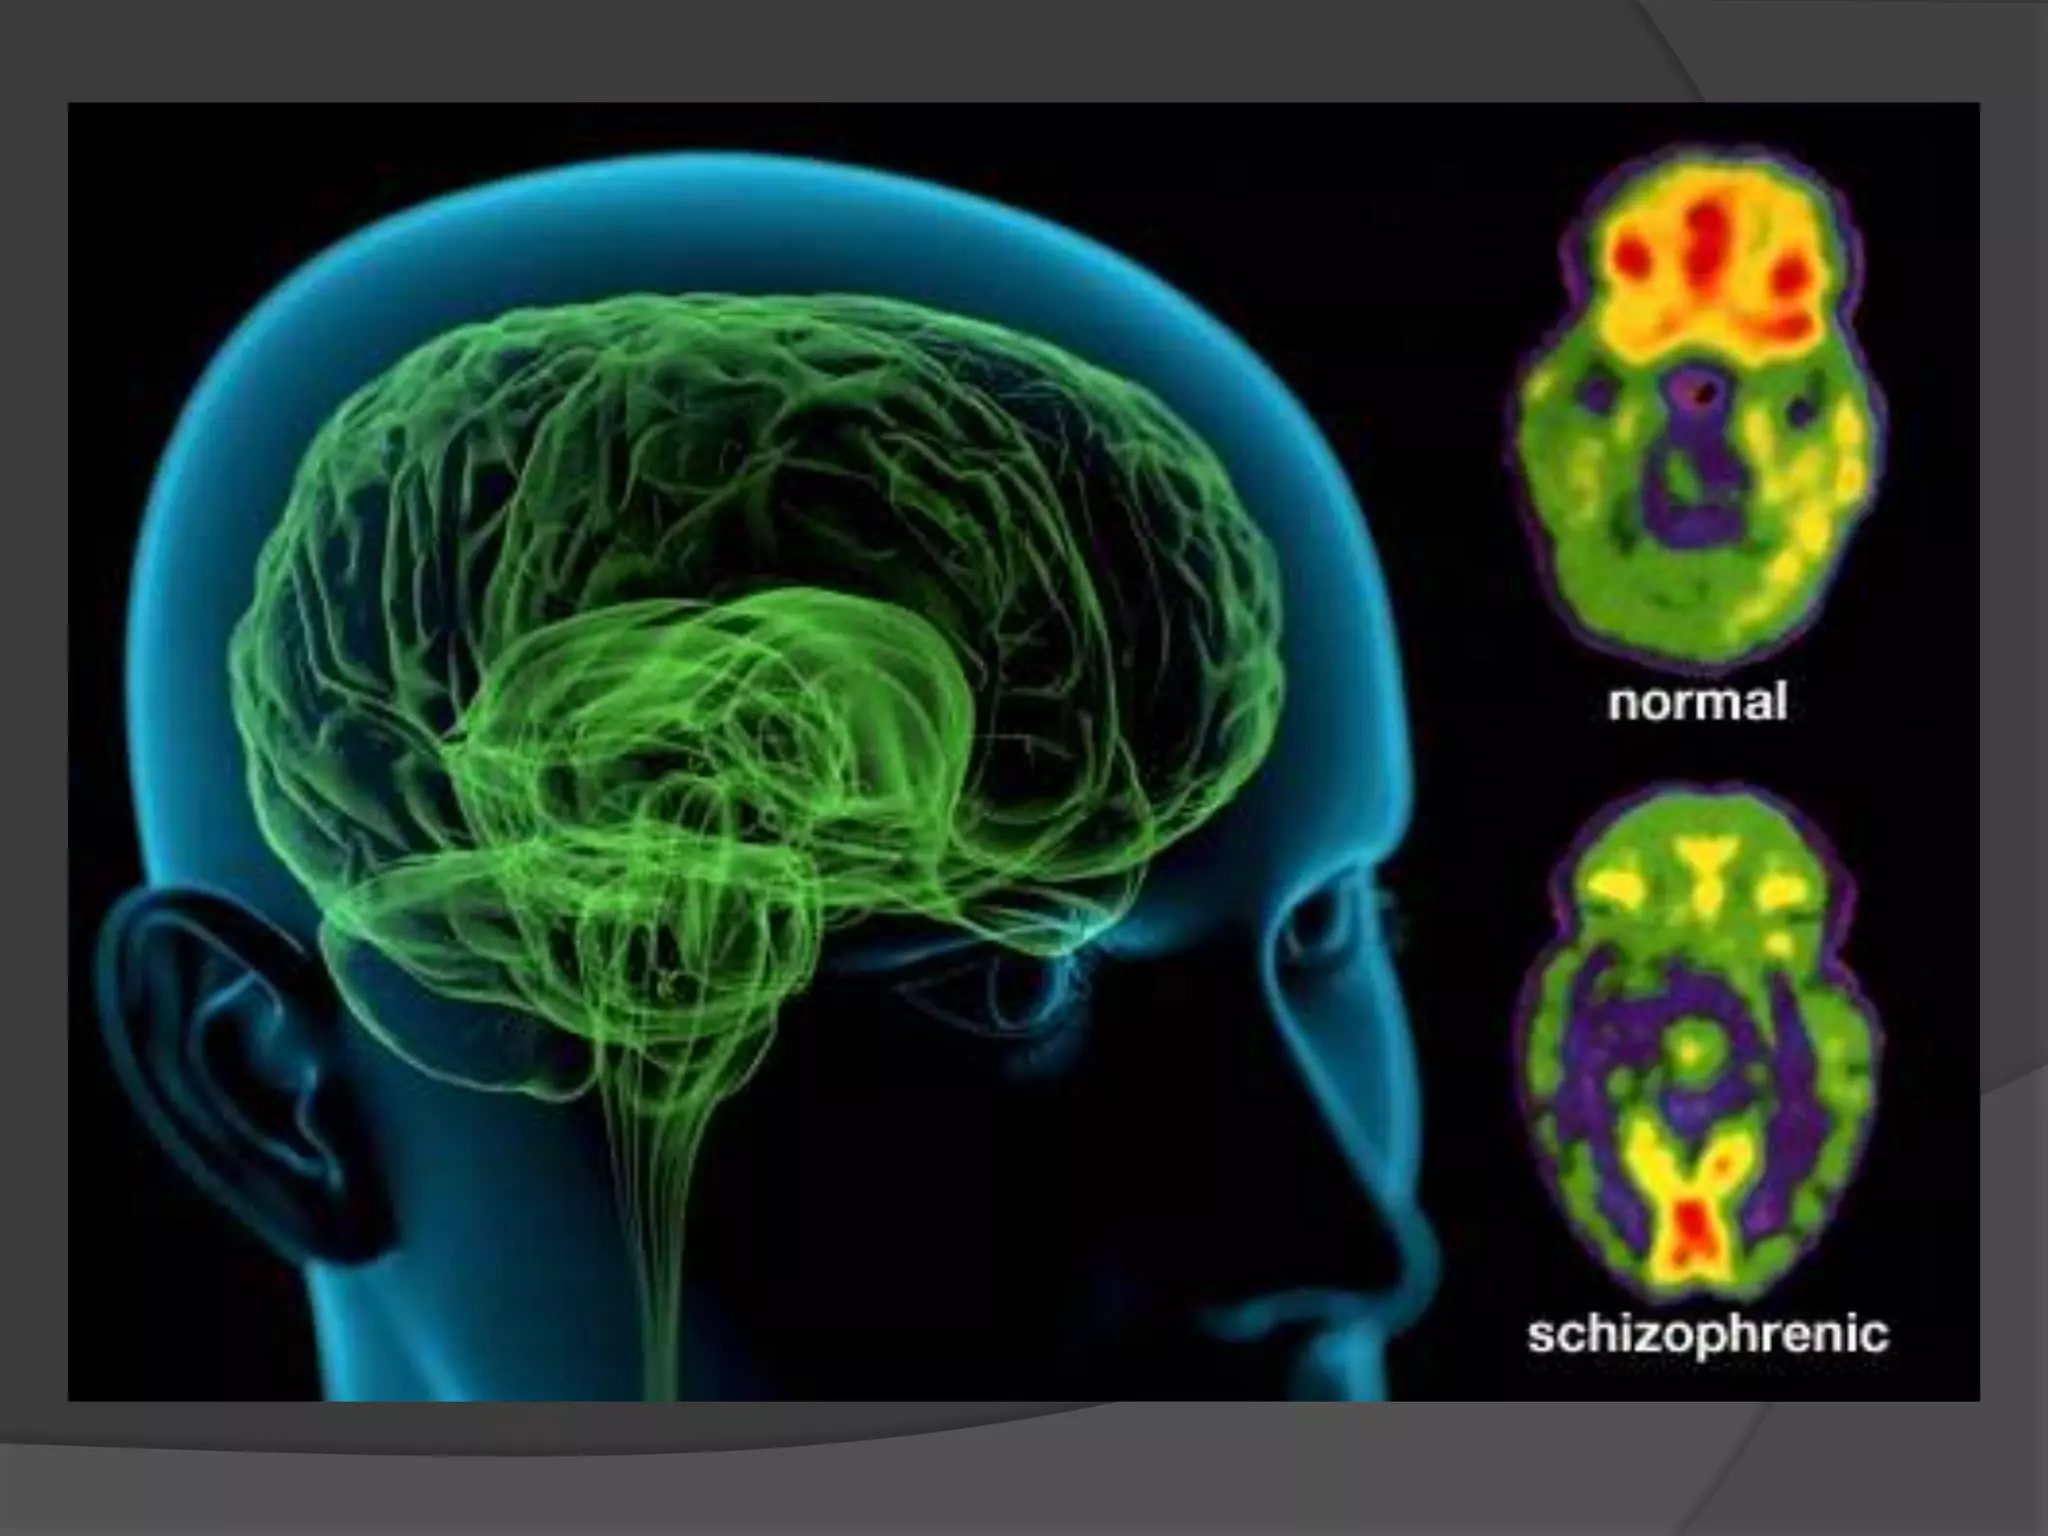

IMAGING IN SCHIZOPHRENIA

Structural imaging



Enlargement of lateral & third ventricles may be static or

progressive.

Frontal lobe abnormalities, particularly prefrontal gray matter

and orbitofrontal regions.

Parietal lobe abnormalities, particularly of the inferior parietal

lobule which includes both supramarginal and angular gyri.

Subcortical abnormalities i.e. cavum septi pellucidum, basal

ganglia, corpus callosum, and thalamus.

All these structural abnormalities may be static or progressive.

Decreased size of medial temporal lobe structures (which

include the amygdala, hippocampus, and parahippocampal

gyrus), and abnormalities of neocortical temporal lobe regions

(superior temporal gyrus).

Hippocampus is not only smaller in size but also functionally

abnormal (disturbed glutamate transmission in functional

scans)

Reduced symmetry in various brain areas may be indicative

of disruption of brain lateralisation during neurodevelopment.

Anatomical & functional deficits in prefrontal cortex.

Functional imaging

Hypofrontality

Functional scans have also revealed lower levels of

phosphomonoester & inorganic phosphate and higher

levels of phophodiester in schiz pts.

NAA levels were also lower in hippocampus and frontal

lobes in pts with schiz.